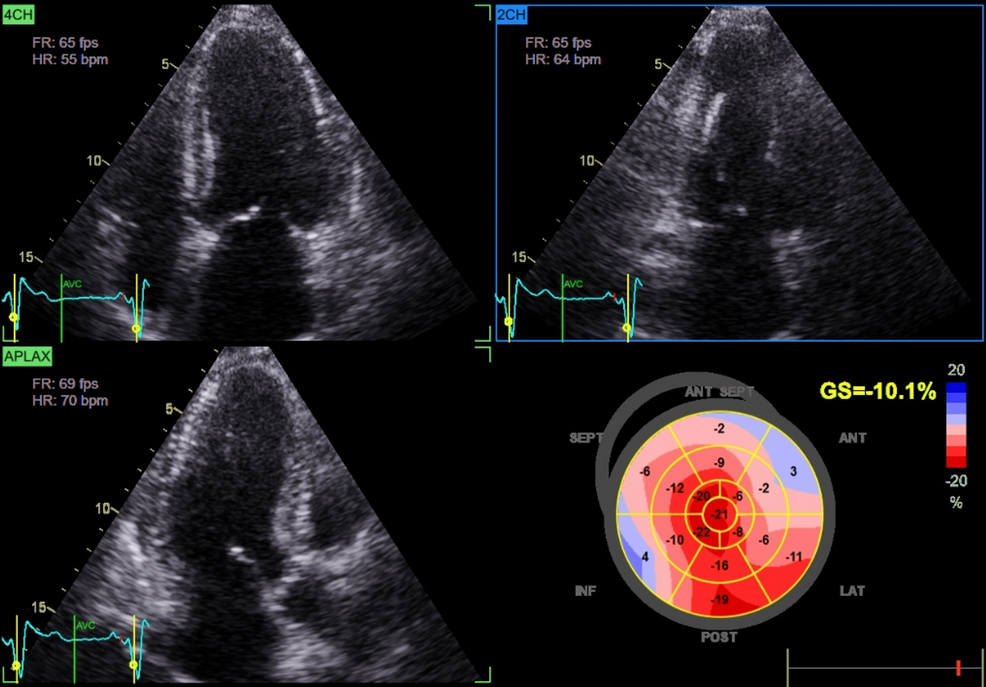

Cardiac assessment supported a diagnosis of HFpEF. Transthoracic echocardiography demonstrated preserved left ventricular ejection fraction (60%), impaired GLS (-10%), and mild concentric left ventricular hypertrophy (Figure 1; Video 2).

Chronic glucocorticoid excess contributes to cardiovascular remodeling via multiple mechanisms. Persistent hypertension and metabolic disturbances promote LVH and diastolic dysfunction. Additionally, glucocorticoid excess induces endothelial dysfunction, insulin resistance, and myocardial fibrosis, impairing ventricular compliance and predisposing to HFpEF [1,6]. Advanced echocardiographic techniques, such as GLS, can detect subclinical systolic dysfunction before overt reductions in LVEF [6]. In our patient, preserved LVEF (60%) coupled with markedly reduced GLS (-10%) and concentric LVH was consistent with HFpEF secondary to chronic cortisol excess, further supported by clinical signs of volume overload such as edema and severe hypertension [7].

Apical sparing and mimicking amyloidosis

An important observation in this case was relative apical sparing despite markedly reduced GLS, a strain pattern classically associated with cardiac amyloidosis [10]. Although infiltrative disease was excluded (negative serum and urine protein electrophoresis with immunofixation), this overlap illustrates how hypercortisolism-induced remodeling can phenocopy amyloidosis on imaging. Recent work has shown that hypercortisolism, beyond metabolic derangements, impairs myocardial mechanics and contractile efficiency [11]. Thus, patients with atypical strain findings should undergo careful endocrine evaluation to avoid misdiagnosis. Ultimately, the recognition that hypercortisolism may produce amyloid-like echocardiographic signatures has both diagnostic and management implications. It broadens the differential diagnosis of HFpEF and stresses the need for a multidisciplinary approach involving endocrinology and cardiology to prevent misdiagnosis and ensure tailored therapy.